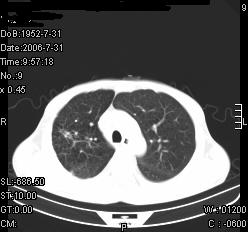

患者,男,54岁,咳嗦,咳痰20天。抗炎治疗2周。现esr76mm/h,目前患者症状明显好转,但发现两次ct片未见明显变化。两次分别做与7.25、7.31。第一次诊断右肺上叶炎症累计胸膜。大家看,从影像上内排除结核吗?

结核的可能性非常大,右上肺病变应该考虑干酪性肺炎。理由:

1.纵隔内多发淋巴结肿大。

2.esr76mm/h。

3.虽经抗炎治疗肺窗病灶有所吸收、减小,但纵隔窗病灶形态、密度、范围无明显变化。如果是单纯的大叶性肺炎,“抗炎治疗2周,目前患者症状明显好转”病灶应该基本消散了,至少也处于吸收消散期,密度变淡、范围变小。同时本病例所示其内的密度不均匀,见多发大小不一空洞样影也不符合大叶性肺炎吸收消散期表现。

病灶特点:片状 索条 结节混杂影,部分融合,密度不均,广泛累及相应胸膜.

临床治疗;二周未吸收.但症状好转.

多考虑:肺结核.